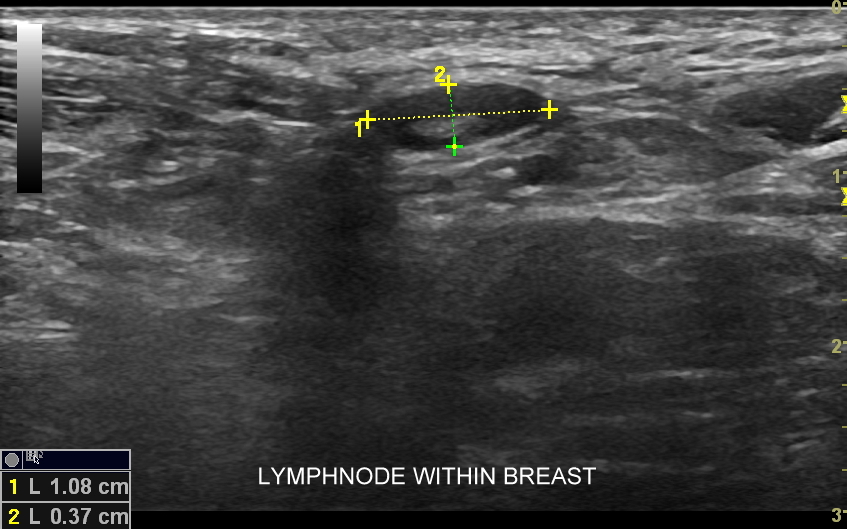

Badanie USG piersi jest podstawową i jedną z najważniejszych metod obrazowania gruczołu piersiowego. Wskazania do jego wykonania obejmują profilaktykę raka gruczołu piersiowego u kobiet oraz wskazania diagnostyczne. Profilaktyczne badanie USG piersi u kobiet wykonywane powinno być regularne raz w roku już nawet od 25 roku życia, w szczególności w przypadku rodzinnego obciążenia onkologicznego. Ze wskazań diagnostycznych badanie USG gruczołu piersiowego przeprowadzane jest w wypadku pojawienia się macalnego guzka piersi, deformacji piersi, jej stwardnienia i bolesności, stanu zapalnego, wycieku z brodawki sutkowej, czy powiększenia się pachowego węzła chłonnego. USG gruczołu sutkowego bywa również uzupełnieniem badania mamograficznego.

Badanie USG piersi z kontrastem (CEUS) jest najnowszą metodą diagnostyczną piersi i rozwinięciem badania multiparametrycznego USG (MPUS). Główną rolą badania CEUS piersi jest zwiększenie precyzji oceny guzków piersi pod kątem kwalifikacji w skali BIRADS, a przez to uniknięcie niepotrzebnych biopsji piersi. W przeciwieństwie do innych metod diagnostycznych zasadniczą zaletą badania CEUS jest możliwość jednoznacznego wykazania lub wykluczenia unaczynienia guzka piersi. Podejrzany guzek, którego unaczynienia lub cech nie można jednoznacznie ocenić w standardowym badaniu USG można poddać badaniu USG z kontrastem. Otóż w przypadku, gdy zmiana nie posiada unaczynienia to nie jest ona nowotworem. Niezależnie od kwalifikacji guzków łagodnych badanie CEUS ma możliwość w wielu wypadkach uwidocznienia ukrytych dodatkowych cech świadczących o złośliwości guzka.